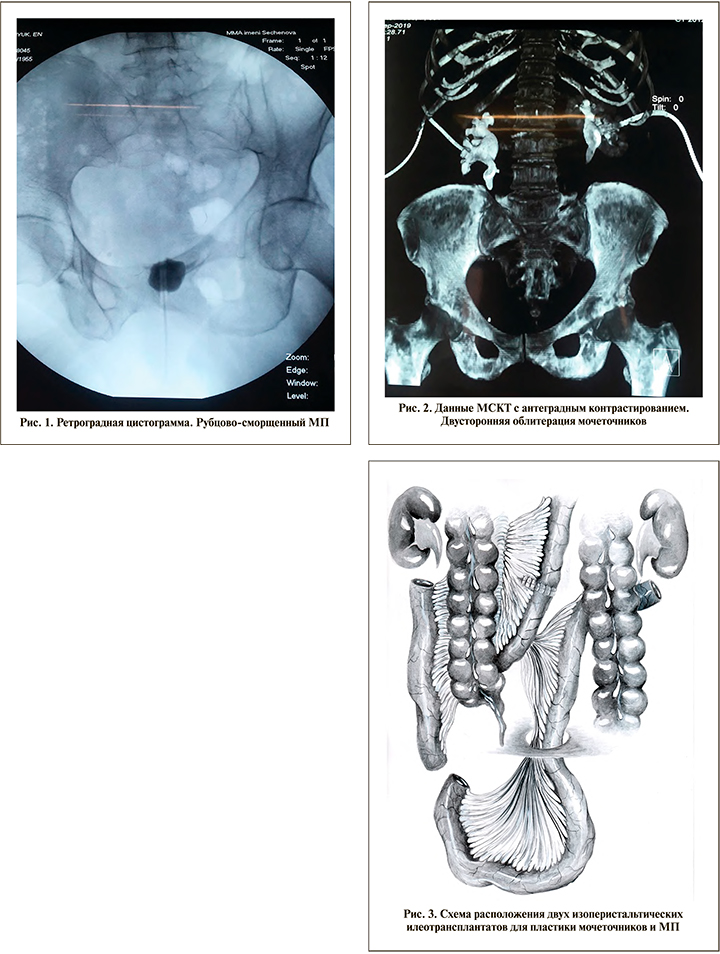

При поступлении: состояние удовлетворительное, температура тела нормальная, гемодинамика стабильная, живот мягкий, умеренно болезненный в нижних отделах. Нефростомические дренажи функционируют. Суточный диурез – 1600–1800 мл. В клиническом анализе крови от 24.09.2019: эр. – 4,82•1012/л; Hb – 132 г/л; л. – 6,23•109/л. Биохимический анализ крови: АлАТ – 9 ЕД/л, АсАТ – 12 ЕД/л, креатинин – 105 мкмоль/л, общий белок – 85,5 г/л, глюкоза – 6 ммоль/л. Общий анализ мочи: реакция кислая; белок – 1,2 г/л; эритроциты – 100–150 в поле зрения; лейкоциты – 20–30–40 в поле зрения. По данным цистографии, объем МП около 15 мл (рис. 1). Мультиспиральная компьютерная томография с антеградным контрастированием выявила двустороннюю облитерацию мочеточников (рис. 2). Забрюшинная клетчатка уплотнена до 38 HU. Объем МП – 17 мл, стенка МП утолщена до 12 мм. Диагностированы интерстициальный цистит с исходом в микроцистис и тяжелая форма болезни Ормонда с поражением обоих мочеточников на всем протяжении.

25.09.2019 бригадой урологов проведена операция. Выполнена нижнесрединная лапаротомия. При ревизии: МП резко уменьшен и представляет собой плотный рубцовый конгломерат; забрюшинная клетчатка с обеих сторон инфильтрирована, уплотнена; мочеточники с трудом дифференцируются, имеют тонкие стенки с участками рубцовых изменений. Органы брюшной полости без патологии. Проведена цистэктомия с удалением правого и большей части левого деструктивно измененных мочеточников. Затем, с отступом 20 см от илеоцекального угла резецирован сегмент подвздошной кишки длиной около 90 см. Проходимость кишки восстановлена аппаратным швом. Трансплантат разделен на два неравных участка: проксимальный, расположенный выше межкишечного анастомоза длиной 25–30 см, и дистальный ниже межкишечного анастомоза длиной 55–60 см. Короткий илеотрансплантат в изоперистальтическом положении проведен через брыжейку восходящего отдела толстой кишки в правый боковой канал. Проксимальный конец более длинного J-образного илеотрансплантата, предназначенного для замещения левого мочеточника и формирования артифициального МП, заглушен и выведен в забрюшинное пространство к области ворот левой почки, где временно фиксирован (рис. 3).